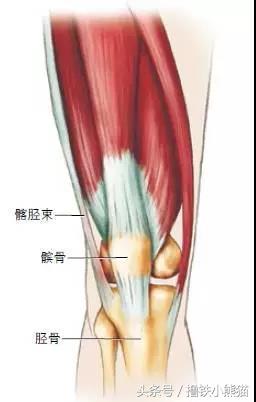

常见原因:髂胫束(ITB)从膝盖侧面到胫骨附着处这段容易发炎,这往往与过度使用膝关节有关,常发生于自行车、跑步和铁人三项运动员中。髂胫束受损和训练量增加的关系最密切。

识别方法:疼痛局限于髂胫束在膝盖外侧的部位;膝盖的其余部位可能无症状。通常情况下,在活动开始的时候疼痛非常轻微,而且未发现有肿胀。通常没有局部软组织肿胀。在膝关节屈伸运动期间,髂胫束可能会绷紧,而且在由前向后活动中受到刺激。偶尔也可能发生髂胫束近端压痛,就在髋关节部位。

治疗方法:髂胫束综合征的治疗方法通常都是非手术方法,首先从休息开始。在治疗这种疾病时,在指导下进行物理治疗非常有用。除了拉伸髂胫束之外,局部理疗法也有帮助,比如对股骨髁外侧(膝盖的外侧)附近的压痛部位使用超声波和电刺激。运动员可以在采取恰当预防措施的情况下,尝试使用10天的消炎药物。注射可的松可能也有帮助。伸展下肢肌肉有助于消除肌张力和刺激。一天冰敷按摩几次。将冰块直接放在膝盖的外轮廓上,应该有助于消除症状。运动员应该通过训练提升下肢的力量,加强臀部肌肉。